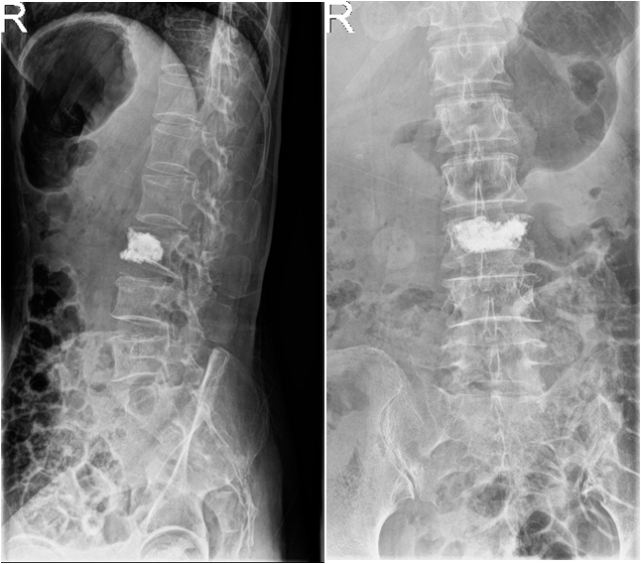

术前x线正位片

术后x光片